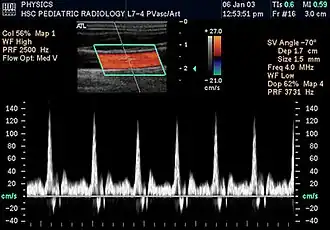

Kidneys

Renal ultrasonography using duplex technique of a normal adult kidney, with the estimation of the systolic velocity (Vs), the diastolic velocity (Vd), acceleration time (AoAT), systolic acceleration (Ao Accel) and resistive index (RI). Red and blue colors in the color box represent flow towards and away from the transducer, respectively. The spectrogram below the B-mode image shows flow velocity (m/s) against time (s) obtained within the range gate. The small flash icons on the spectrogram represent initiation of the flow measurement.

Doppler ultrasonography is widely used in renal ultrasonography. Renal vessels are easily depicted by the color Doppler technique in order to evaluate perfusion. Applying spectral Doppler to the renal artery and selected interlobular arteries, peak systolic velocities, resistive index, and acceleration curves can be estimated (Figure 4) (e.g., peak systolic velocity of the renal artery above 180 cm/s is a predictor of renal artery stenosis of more than 60%, and a resistive index, which is a calculated from peak systolic and end systolic velocity, above 0.70 is indicative of abnormal renovascular resistance).[12]